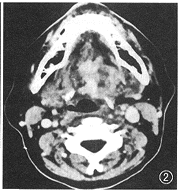

图2 口底ACC,形态不规则呈无定形,见隙就钻

2.浸润性生长: 肿瘤大部分形态极不规则呈无定形,有见隙就“钻”的特点(图2),并浸润周围组织,因此边界常不清晰,可伴骨质浸润破坏[5]。如肿瘤比较小,局限于大涎腺内,则不表现此种特点;如生长在舌上的肿瘤,虽有浸润性生长,但因与周围肌肉对比较差,故CT上表现不甚明显,肿瘤常呈类圆形。不管影像上肿瘤形态如何不同,在病理上肿瘤均表现为浸润性生长,侵犯局部横纹肌或脉管,因此临床决定手术范围常感困难。文献报道,ACC易在首次治疗后的10~20年复发,一些作者认为无论这些病人有多长的无瘤期,最终将死于ACC[2,3]。

4.黏膜下生长:小涎腺通常分布于头颈部的黏膜下,肿瘤容易向深部组织浸润而很少穿破黏膜,也为特点之一(图1),如发生在舌、腭部、口底、颊等部位的ACC与发生在此处较常见的鳞状细胞癌不同,后者局部黏膜常被破坏,以此也可作为鉴别。